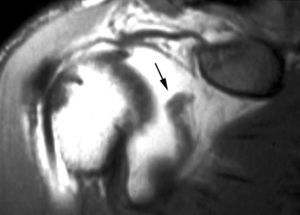

Una vez que se ha producido la lesión SLAP II-b, la continuación de las fuerzas de extrema rotación externa conducen a una torsión repetitiva del tendón supraespinoso, que lleva a una rotura parcial o completa del mismo (fig. 36).

Fig. 36.--GIRD (glenohumeral internal rotation deficit). Resonancia magnética (RM) coronal oblicua T2 con supresión de grasa donde se aprecia una lesión de SLAP (superior labrum anterior posterior) (flecha larga), una rotura parcial del supraespinoso (cabeza de flecha) y un engrosamiento capsular inferior (flechas cortas).

Finalmente, otro mecanismo de microinestabilidad descrito es el producido por la tracción hacia delante y abajo del TLB, producido durante la fase de deceleración. Este mecanismo puede llegar también a la producción de una lesión de SLAP con extensión anterior (SLAP II-a) (fig. 37).